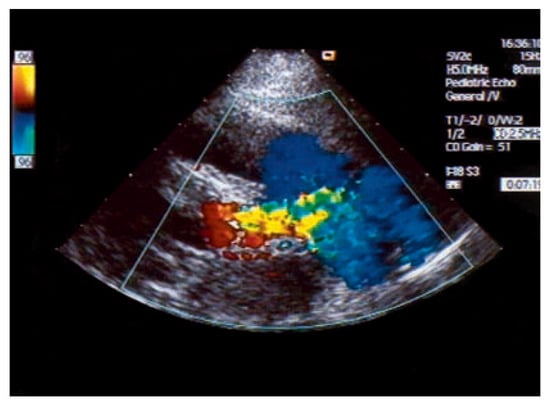

An otherwise healthy 13-year-old girl was referred to the pediatric cardiology outpatient clinic for evaluation of a newly observed systolic murmur. She was normally physically active without symptoms on exertion except for one episode of syncope two months earlier. She then was riding a bike and on climbing off the bike she was observed to hyperventilate, had parestesias of both hands followed by a short loss of consciousness. Family history was negative for any cardiac event. Clinically the systolic murmur was judged a functional ejection murmur but an Echo was done and revealed an enlarged (6 mm) right coronary artery (Figure 3) with huge collaterals especially in the septal region (Figure 4), the origin of the left coronary artery was seen in the pulmonary trunk with turbulent retrograde flow in the color Doppler (Figure 5). LV ejection fraction was 68% but the LV was slightly dilated with a mild mitral regurgitation. Cardiac catheterisation confirmed the suspected anomalous origin of the left coronary artery from the pulmonary trunk (Figure 1 and Figure 2), the patient was advised to undergo surgical correction with reimplantation of the left coronary artery in the aorta.

Figure 3. Superior short axis echo view showing origin of the massively dilated right coronary artery from the aorta in usual position.